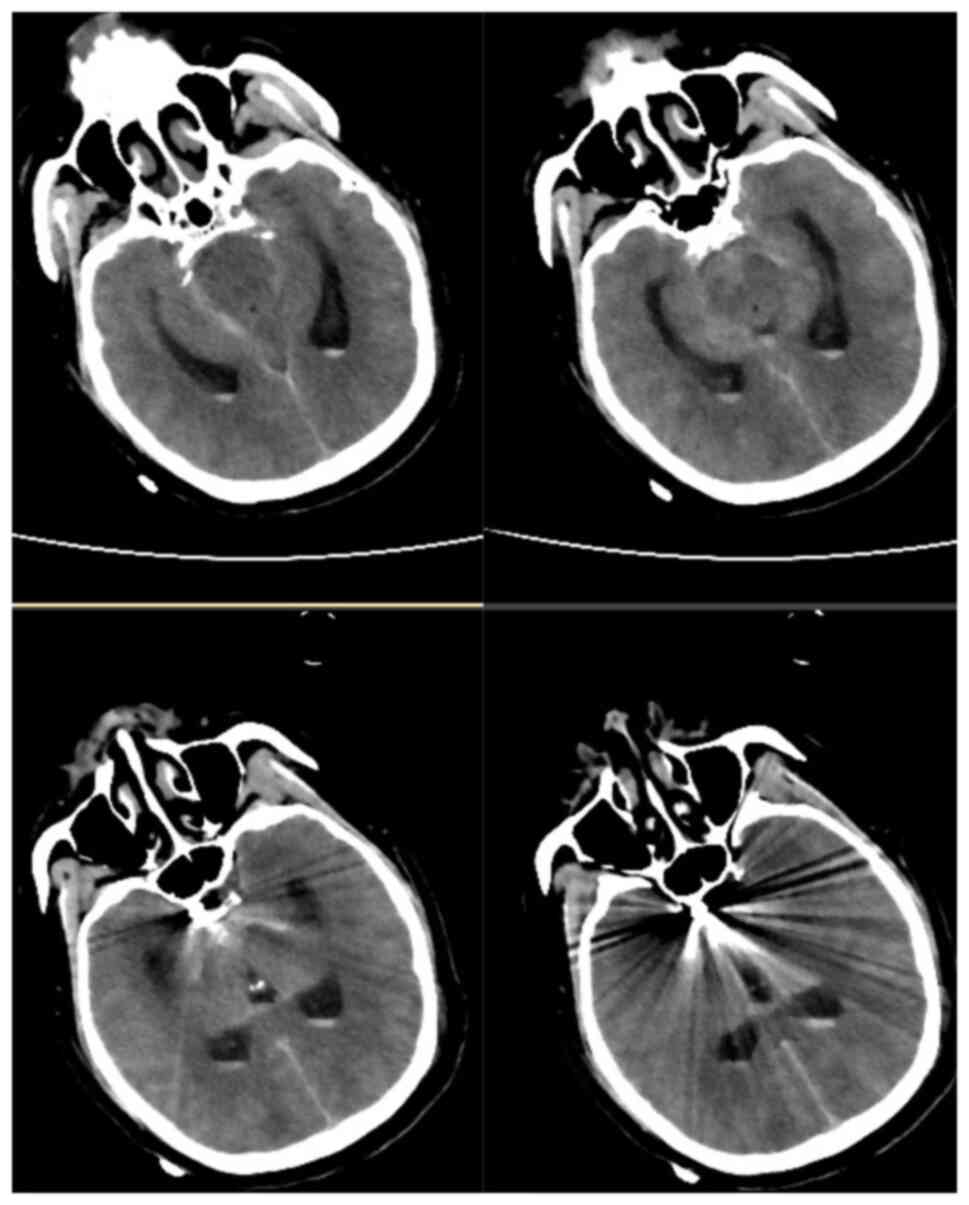

A 40-year-old male patient with a history of hypertension presented to the emergency department of Peking University People's Hospital (Beijing, China) in December 2019 with the complaint of headache for one day, sudden onset of nausea, vomiting and loss of consciousness for 4 h. Neurological examination revealed a Glasgow Coma Scale (GCS) score of 14 (E3V6M5). The patient was a habitual drinker and reported that no immediate family members had experienced any similar cerebrovascular events. The patient had no history of trauma, lumbar puncture or bleeding disorders. The patient was admitted to the emergency department of Peking University People's Hospital (Beijing, China). His blood pressure was controlled through the infusion of urapidil hydrochloride (2-4 ml/h) and his vital signs were stabilized using monitoring equipment and nimodipine administration (2-4 ml/h, 14 days), as described previously (6,7). Cranial computed tomography (CT) and CT angiography (CTA) were performed at the earliest. Brain CT and CTA (Fig. 1A and B) indicated diffuse SAH and an aneurysm in the right internal carotid artery. Thus, a digital subtraction angiography (DSA) examination was scheduled immediately. DSA revealed that the aneurysm was located in the inferior wall of the C5 segment of the right internal carotid artery, with the following characteristics: Aneurysm neck 3 mm and diameter 4x6 mm (Fig. 1C). The patient was placed under general anesthesia 9 h after the bleeding occurred and the intracranial aneurysm was embolized using a coil interventional embolization technique. DSA indicated that the patient's aneurysm was densely packed without contrast retention (Fig. 2A and B). The patient was diagnosed with a right internal carotid artery aneurysm and hypertension.

Figure 1

Preoperative imaging examination of the patient. (A) Initial brain CT showing diffuse subarachnoid hemorrhage. (B) Reconstructive CT angiogram and (C) digital subtraction angiography displaying the C5 segment of the right internal carotid artery aneurysm (red arrows). CT, computed tomography.

After the operation, the patient was transferred to the intensive care unit with tracheal intubation. Following regaining of consciousness and stability of vital signs, the tracheal intubation was removed and the patient was transferred to the general ward on the second day after the operation. The patient was awake and his GCS score was 15 points. The muscle strength assessment was using Lovett's grading approach (8), the muscle strength of both upper limbs of the patient was normal, while the muscle strength of both lower limbs was grade 0, but leg sensation of the patient was normal. No new hemorrhage was detected in the re-examined head CT area on the first day after surgery (Fig. 3). To determine whether the patient's paraplegia was related to the thoracolumbosacral spine, the patient underwent thoracic spine (5 days after the surgery) and lumbosacral spine (4 days after the surgery) magnetic resonance imaging (MRI) examination and lower extremity venous ultrasonography (10 days after the surgery). The thoracic spine MRI scan indicated mild degeneration of the thoracic spine, mild kyphosis of the T4/5 and T5/6 intervertebral discs and mild right kyphosis of the T7/8 intervertebral disc. T3 and T10 vertebral hemangiomas were suspected, as indicated by the red arrow in Fig. 4. The lumbosacral spine MRI scan revealed slight hematoma in the subarachnoid space below the L2 level, as indicated by the red arrow in Fig. 5.

Figure 3

Cranial computed tomography on the first day after surgery. No new hemorrhage was detected in the re-examined head CT area.